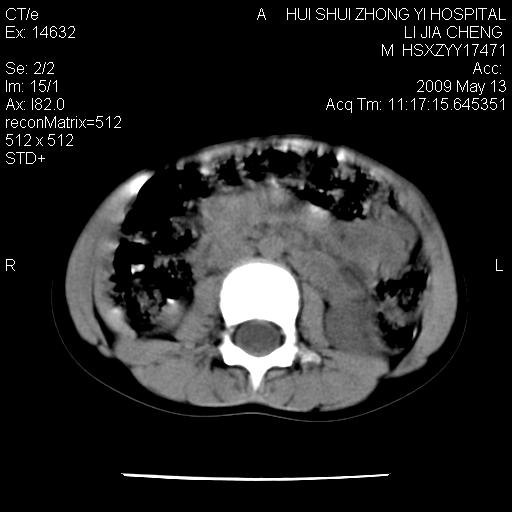

标题: PED1887:男性,6岁。反复脐周疼痛2年余。请各位老师看下腹 [打印本页]

标题: PED1887:男性,6岁。反复脐周疼痛2年余。请各位老师看下腹

该患者可自行好转,大小便未见异常,化验:便未见虫卵,血常规:wbc:8000;淋巴3600,中性45%

肠道准备不足,im15---------------------18左侧腹腔病变?

肠管管壁均匀增厚,炎性可能

考虑腹疝可能。

是小肠,壁稍厚可能是肠腔未很好充盈所致,腹部ct扫描未见明显异常。